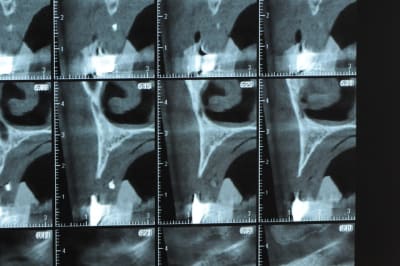

avant de faire la tomosynthèse je comprenais pas pourquoi j'avais aussi peu de contraste.

le patient ne souhaite pas, ou ne peut pas se faire poser 6 implants en haut, donc...overdenture sur 4. (si possible)

Ce n'est pas vraiment un consensus mais plutot du bon sens. Si tu as une crête en profil de lame de couteau cela signifie que tu as une fusion des corticales vestibulaire et palatine et donc absence de spongieux, ce qui comme tu le sais n'est pas indiqué en implanto (cj os de marbre par exemple)

Il me semble que Palti ou encore Szmukler-Moncler recommandent un minimum de 2-3mm. Si c'est plus fin, greffe d'apposition et GBR.

Dans ton cas il te faudrait abaisser la crête de 3 bons mm pour arriver à cette épaisseur.

Une petite étude de ton cas D57

Sous réserves bien sur de voir l’animal en vrai

Les zones exploitables radiologiquement parlant:

Coupes implant

2,3 40100

4,96 35130 avec sinus lift mais difficile

5,25 35150

6,02 35130

6,78 35115 après réduction de hauteur de crête

7,26 35115 après réduction de hauteur de crête

8,51 35150

10,43 40115 ou 50115

11,10 40115

Ce qui nous fait 9 implants possible évidement avec un comblement de sinus on augmenterait encore les zones implantable mais ce n’est pas le but recherché, avec 8 (4+4) il doit être possible de faire une belle barre support de complet